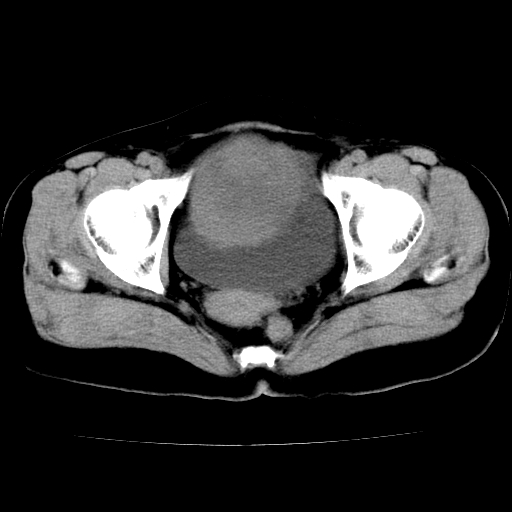

标题: CT24785:女,62岁,发现下腹部肿物半年。 [打印本页]

标题: CT24785:女,62岁,发现下腹部肿物半年。

女,62岁,发现下腹部肿物半年,下腹部不适。

老年女性患者,盆腔囊实性占位,ct增强不均匀强化,未见壁结节,未见腹水及盆腔积液,考虑附件囊腺瘤可能性大!